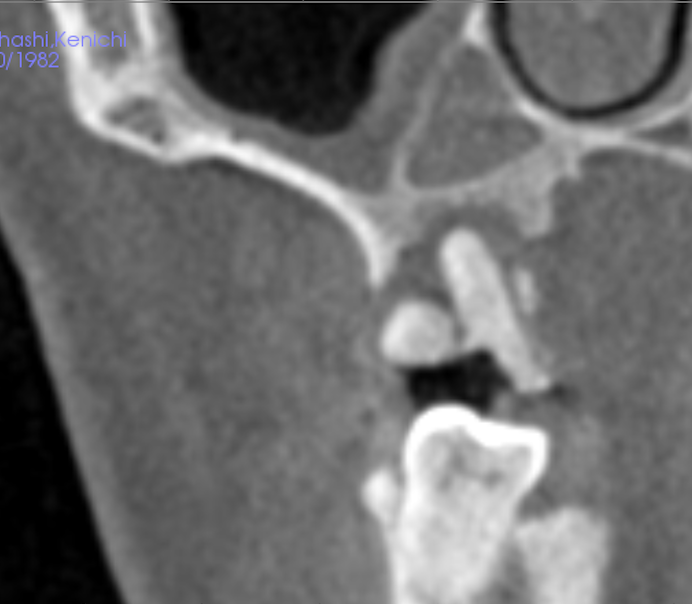

治療前

このケースでは上顎洞の手術をする際にリスクとなる、後上歯槽動脈の位置と隔壁や上顎洞の形態的にサイナスリフトが非常に困難な状況でした。合わせて、患者様の希望により可能な限り治療期間を短くしてほしいとのことも踏まえてソケットリフトによる抜歯即時インプラント埋入術を行いました。